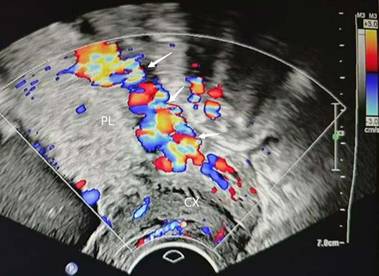

Figure 3

irregular intraplacental vascularization of posterior placenta(arrow) PL, placenta. CX, cervix.

Ultrasound (US) and magnetic resonance imaging (MRI) have shown high diagnostic performance in the detection of PAS[17-19]. Ultrasound serves as the primary diagnostic tool for PAS; however, current clinical sonographic criteria are primarily validated for anterior PAS cases complicated by placenta previa. When the placenta invades the posterior uterine wall, the diagnostic accuracy of prenatal ultrasound in detecting characteristic signs remains uncertain[17, 18, 20]. Dellapiana et al. reported that the application of standard sonographic criteria results in a low antenatal detection rate for posterior PAS[21]. For optimal ultrasound diagnosis of posterior PAS, the recommended gestational window for initial screening is between 25 and 28 weeks. This timing is advantageous because: the uterine wall and placental architecture are more clearly visualized at this stage, the amniotic fluid-to-fetal size ratio is more favorable, and the posterior implantation site becomes more accessible for evaluation[22]. The ultrasound markers of PAS include: (1) Loss or irregularity of the hypoechoic area between the uterus and placenta, the 'retroplacental clear zone' (Figure 1), (2) Myometrial thickness <1mm, (3)placental lacunae with high velocity flow (>15cm/s) (Figure 2), (4)Thinning or interruption of the uterine serosa-bladder wall interface, (5) Placental bulge, (6) Exophytic mass,(7) Subplacental and/or uterovesical hypervascularity, (8) Loss of vascular arch parallel to the basal plate and irregular intraplacental vascularization (Figure 3)[3, 23]. After excluding the two bladder line-dependent criteria, the following four key sonographic features were consistently observed in the posterior placental region: loss or irregularity of the hypoechoic area between the uterus and placenta, myometrial thickness <1mm, placental lacunae with high velocity flow (>15cm/s), and Loss of vascular arch parallel to the basal plate and irregular intraplacental vascularization[22]. Many authors have adopted a two-criteria system in their articles: PAS is diagnosed when there are two or more ultrasonic signs present[22, 24]. The two-criteria system has a high sensitivity (60.0%), specificity (98.9%), and positive predictive value (85.7%). Moreover, when using a single criterion or the optimal criterion, there is no improvement in the maternal outcomes of true positive and false negative cases, which confirms the reliability of the two-criteria system[22]. A retrospective study has found that the sensitivity of ultrasound in detecting anterior PAS is as high as 81 - 93%[18]. Other studies have also validated this discrepancy. The ADoPAD (Antenatal Diagnosis of Placental Attachment Disorders) Study Group reported that prenatal ultrasound detected 92% of all anterior PAS cases, which was significantly higher than the 62% detection rate for posterior PAS[11]. The detection rates of PAS in anterior and posterior placentas were reported by Pilloni et al. as 89.7% and 50% respectively, under the application of the two - criteria system[24]. However, in a recent study, after excluding patients with placenta previa, only 30% of posterior placenta PAS cases were diagnosed through prenatal ultrasound screening. This suggests that compared with anterior PAS, ultrasound examination has lower sensitivity for posterior PAS[21]. An independent evaluation of the sensitivity of individual ultrasound signs for pathologically confirmed posterior and anterior PAS was conducted. The sensitivities of retroplacental lacunae, vascular congestion, myometrial thinning, and absence of hypoechoic areas in detecting posterior wall PAS ranged from 24% to 42%. However, multiple studies have demonstrated that the absence/irregularity of the retroplacental clear zone shows the highest sensitivity and negative predictive value for posterior placenta accreta - comparable to or even exceeding that of the dual-criteria system. These findings confirm the diagnostic importance of this specific criterion for posterior placenta accreta, while other criteria exhibit significantly lower sensitivities compared to the dual-criteria system[22, 24]. This divergence primarily stems from hemodynamic differences, as the posterior uterine wall's lower segment demonstrates greater vascularity compared to the anterior wall. Sonographically, the retroplacental clear zone shows better echogenic contrast with posterior placental positioning than with anterior implantation. Consequently, when placental invasion disrupts the retroplacental clear zone's integrity, sonographic abnormalities become more detectable on the posterior uterine wall. This diagnostic advantage is most evident between 26 and 28 weeks of gestation[24]. In summary, ultrasound demonstrates suboptimal sensitivity for detecting posterior PAS. As the first-line imaging modality, its diagnostic performance is limited by three key factors: (1) operator-dependent variability, (2) reduced efficacy in obese patients, and (3) poor detection of posterior placental invasion. These limitations collectively compromise both the accuracy and clinical utility of ultrasound for posterior PAS diagnosis. Furthermore, current research on posterior PAS remains constrained by small sample sizes, highlighting the need for larger-scale studies to validate existing findings[22].